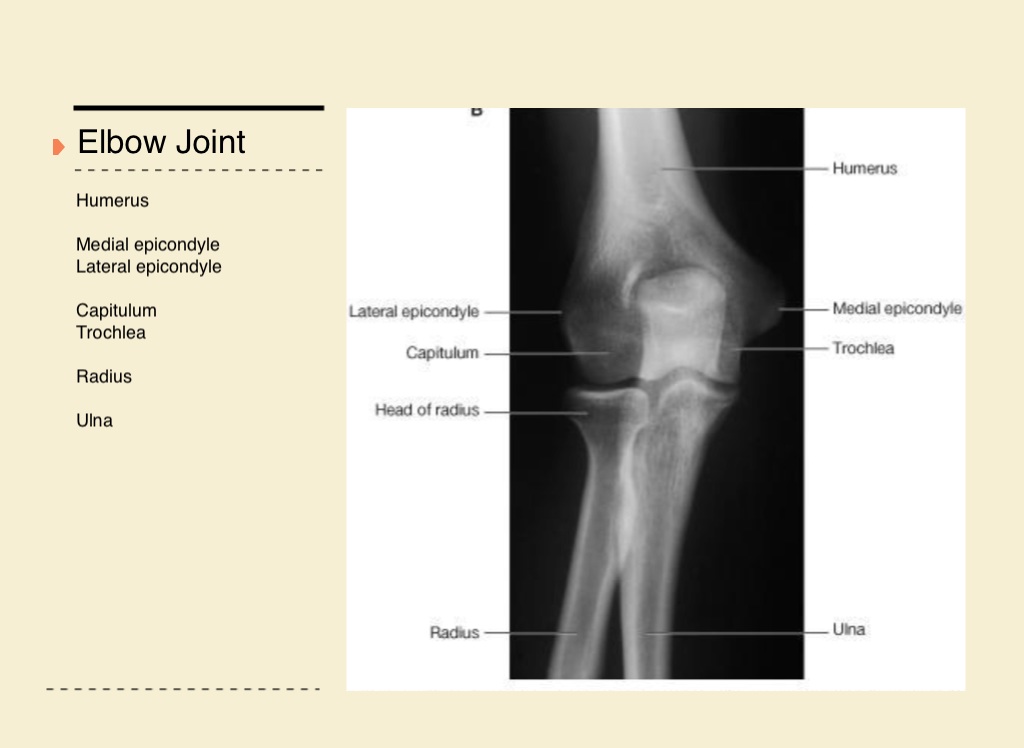

Elbow Joint

Humerus

Medial epicondyle

Lateral epicondyle

Capitulum

Trochlea

Radius

Ulna